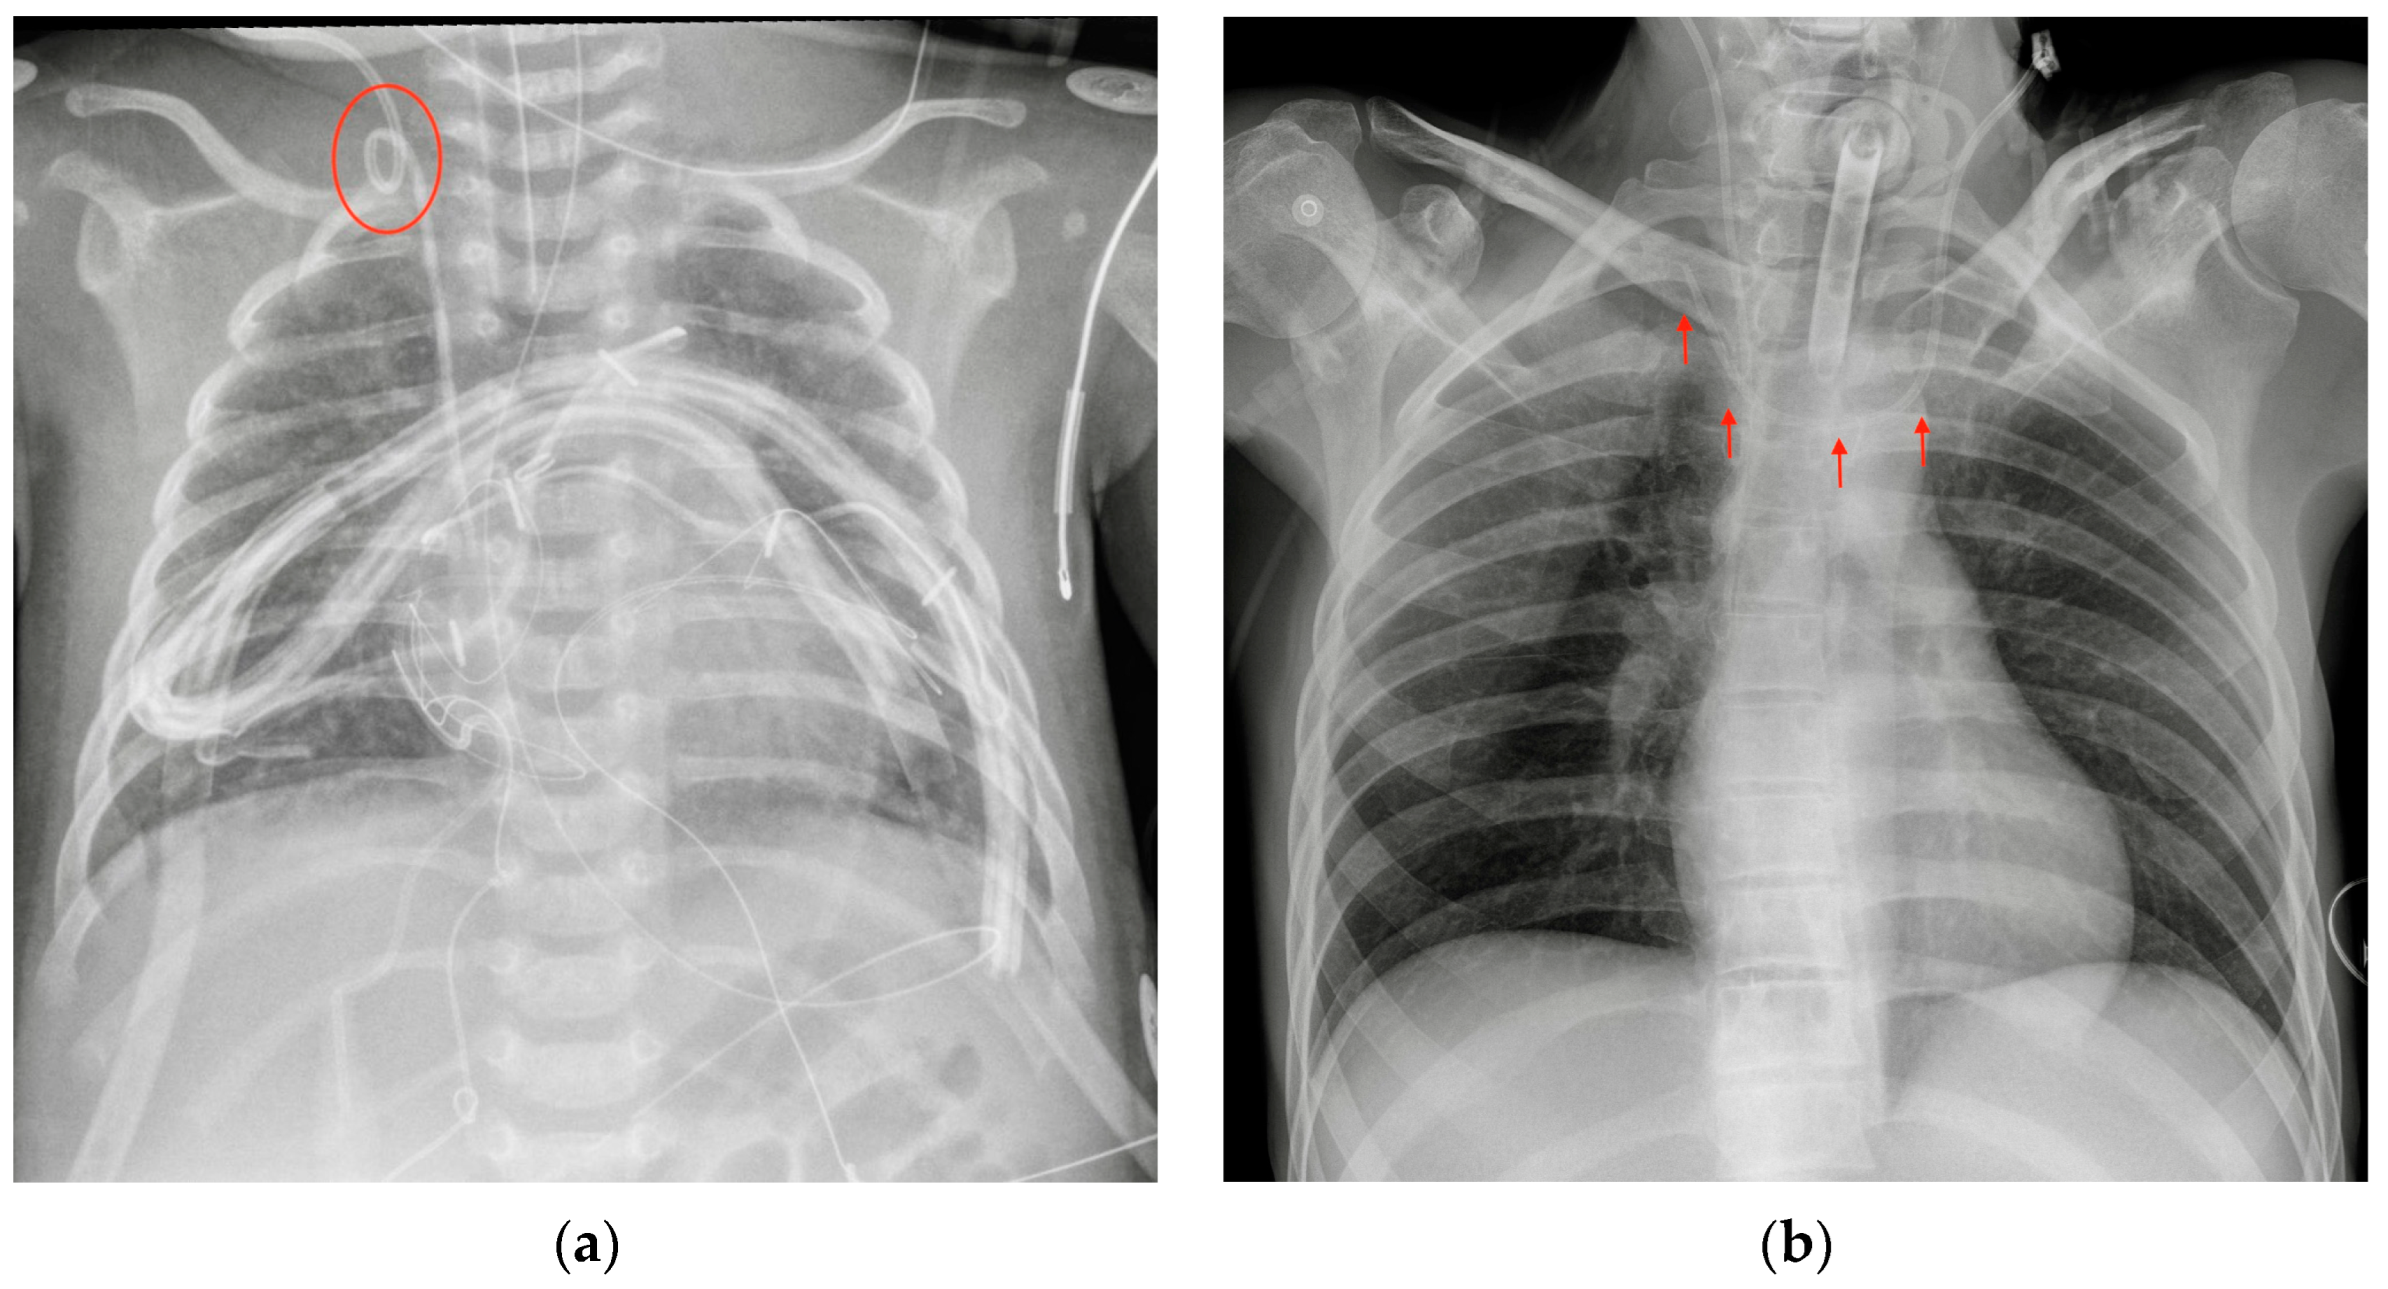

The most common CXR-detectable complications are pneumothorax, malposition (looping, inferior vena cava (IVC) positioning of the tip, wrong thoracic vein positioning), or, less often, vascular perforation, with the catheter located inside the thorax (Figure 3, Figure 4 and Figure 5, Table 2) [6,7].

Figure 4.

Malpositioned CVCs. (a) Right jugular-inserted CVC looping against the vessel wall and ending inside the SVC (red circle). (b) Left jugular CVC with tip ending inside the right subclavian vein (red arrows).